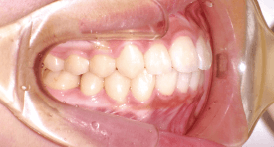

Before Braces - 治療前 -

犬歯と第一大臼歯のⅡ級関係が見られます。

また、前歯に過度なジェットが見られます。